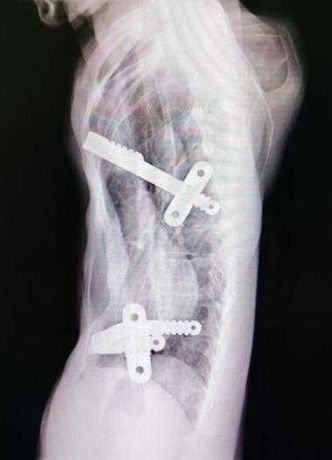

The chest wall shows a significant, asymmetrical depression with severe heart compression. Additionally, one of the bars inserted during the Nuss procedure has shifted out of position.

Our analysis indicates that the specific reasons for the failure of the patient's first surgery are as follow: 1. improper placement of the bars, which were not positioned at the bottom of the depression to provide adequate support; 2. unsuitable length and curvature of the bars; 3. flawed fixation, which resulted in one of the bars shifting out of position.